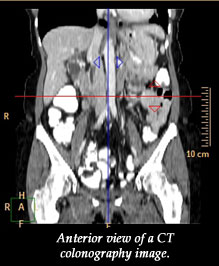

The research looked at the technique of CT colonography which takes images with X-rays to provide cross-sectional snapshots of various parts of the body.

CT colonography is an important screen for colorectal cancer, the third most common form of cancer in the United States and the second leading cause of cancer death. Rizwan Aslam, an assistant clinical professor of radiology at UCSF, and his colleagues evaluated 35 people who underwent CT colonography at the San Francisco Veterans Administration Hospital.

They wanted to see if in scanning the abdomens of these 35 people, CT colonography would also collect data on the condition of their spine. They hypothesized that this spine data would allow them to measure bone mineral density - an indicator of risk for osteoporosis or "porous bone," a disease in which bones become fragile and prone to fracture. According to the National Institutes of Health, some 10 million Americans already have osteoporosis and 34 million more have low bone mass and are at increased risk for the disease.